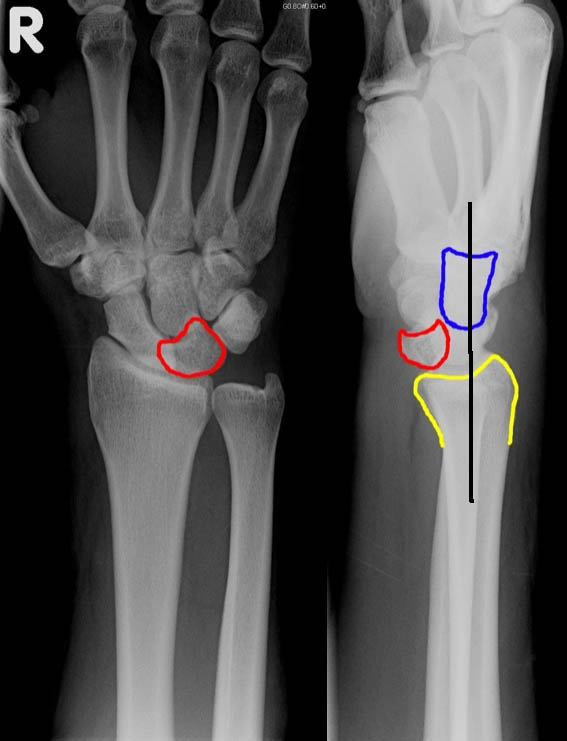

- Lunate Dislocation

- PA view

- Lunate has triangular shape ("piece-of-pie sign")

- Lateral view

- Lunate is pushed off the radius into the palm ("spilled teacup" sign)